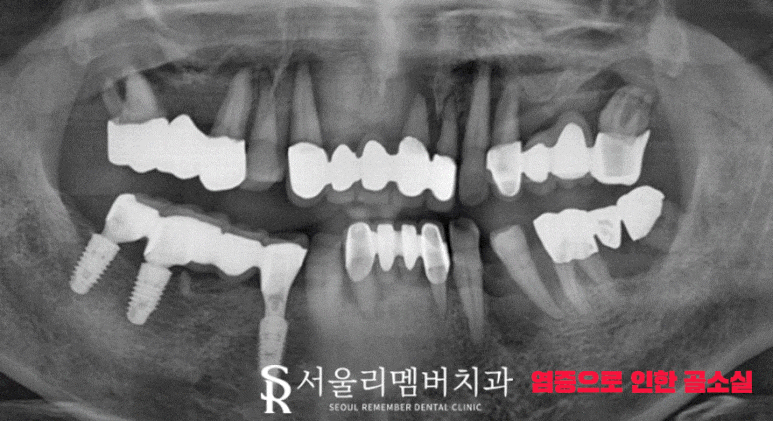

정확한 진단을 위해 엑스레이 촬영을 했는데요.

염증 때문에 하얗게 보여야 될 뿌리 부근의 조직이 검은색으로 바뀌어 있었습니다.

즉, 뼈가 녹아서 더는 지지력을 받을 수 없었죠.

자연 발치가 이루어져도 이상하지 않을 정도로 골소실 정도가 심각했습니다.

따라서 살릴 수 있는 몇 개의 치아와 이미 임플란트가 심어져 있던 오른쪽 아래 어금니를 제외하곤

전체 임플란트를 통해 잃어버린 기능을 되찾아주기로 계획했습니다.